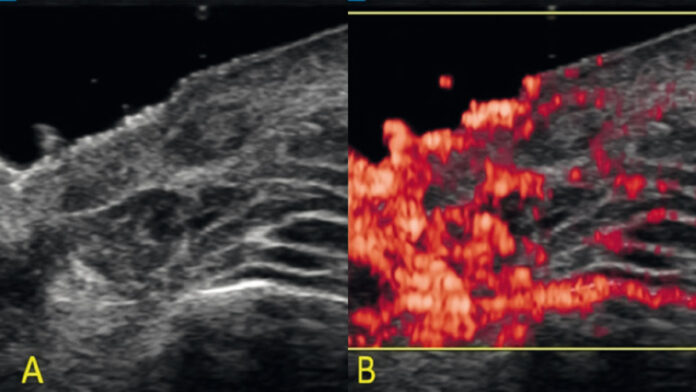

The tear trough is a particularly challenging anatomical area whose appearance greatly affects the aesthetics of the face. Rejuvenating procedures performed in this area are growing in popularity, and with their number, the risk of complications is also increasing. Accurate diagnosis of changes in the tear trough is a clinical challenge. High-frequency ultrasound is an imaging method that can be helpful in this regard.

The study aimed to demonstrate the utility of highfrequency ultrasonography in diagnosing complications in the tear trough area in a woman who had been given a polynucleotide-based biostimulator.

Based on the case described, it can be concluded that high-frequency ultrasonography is a useful method in the diagnosis of complications after procedures in the tear trough area. It allows for the differentiation of focal lesions and their measurement. Incorporating this method into everyday aesthetic medicine practice increases patient safety and the effectiveness of interventions.